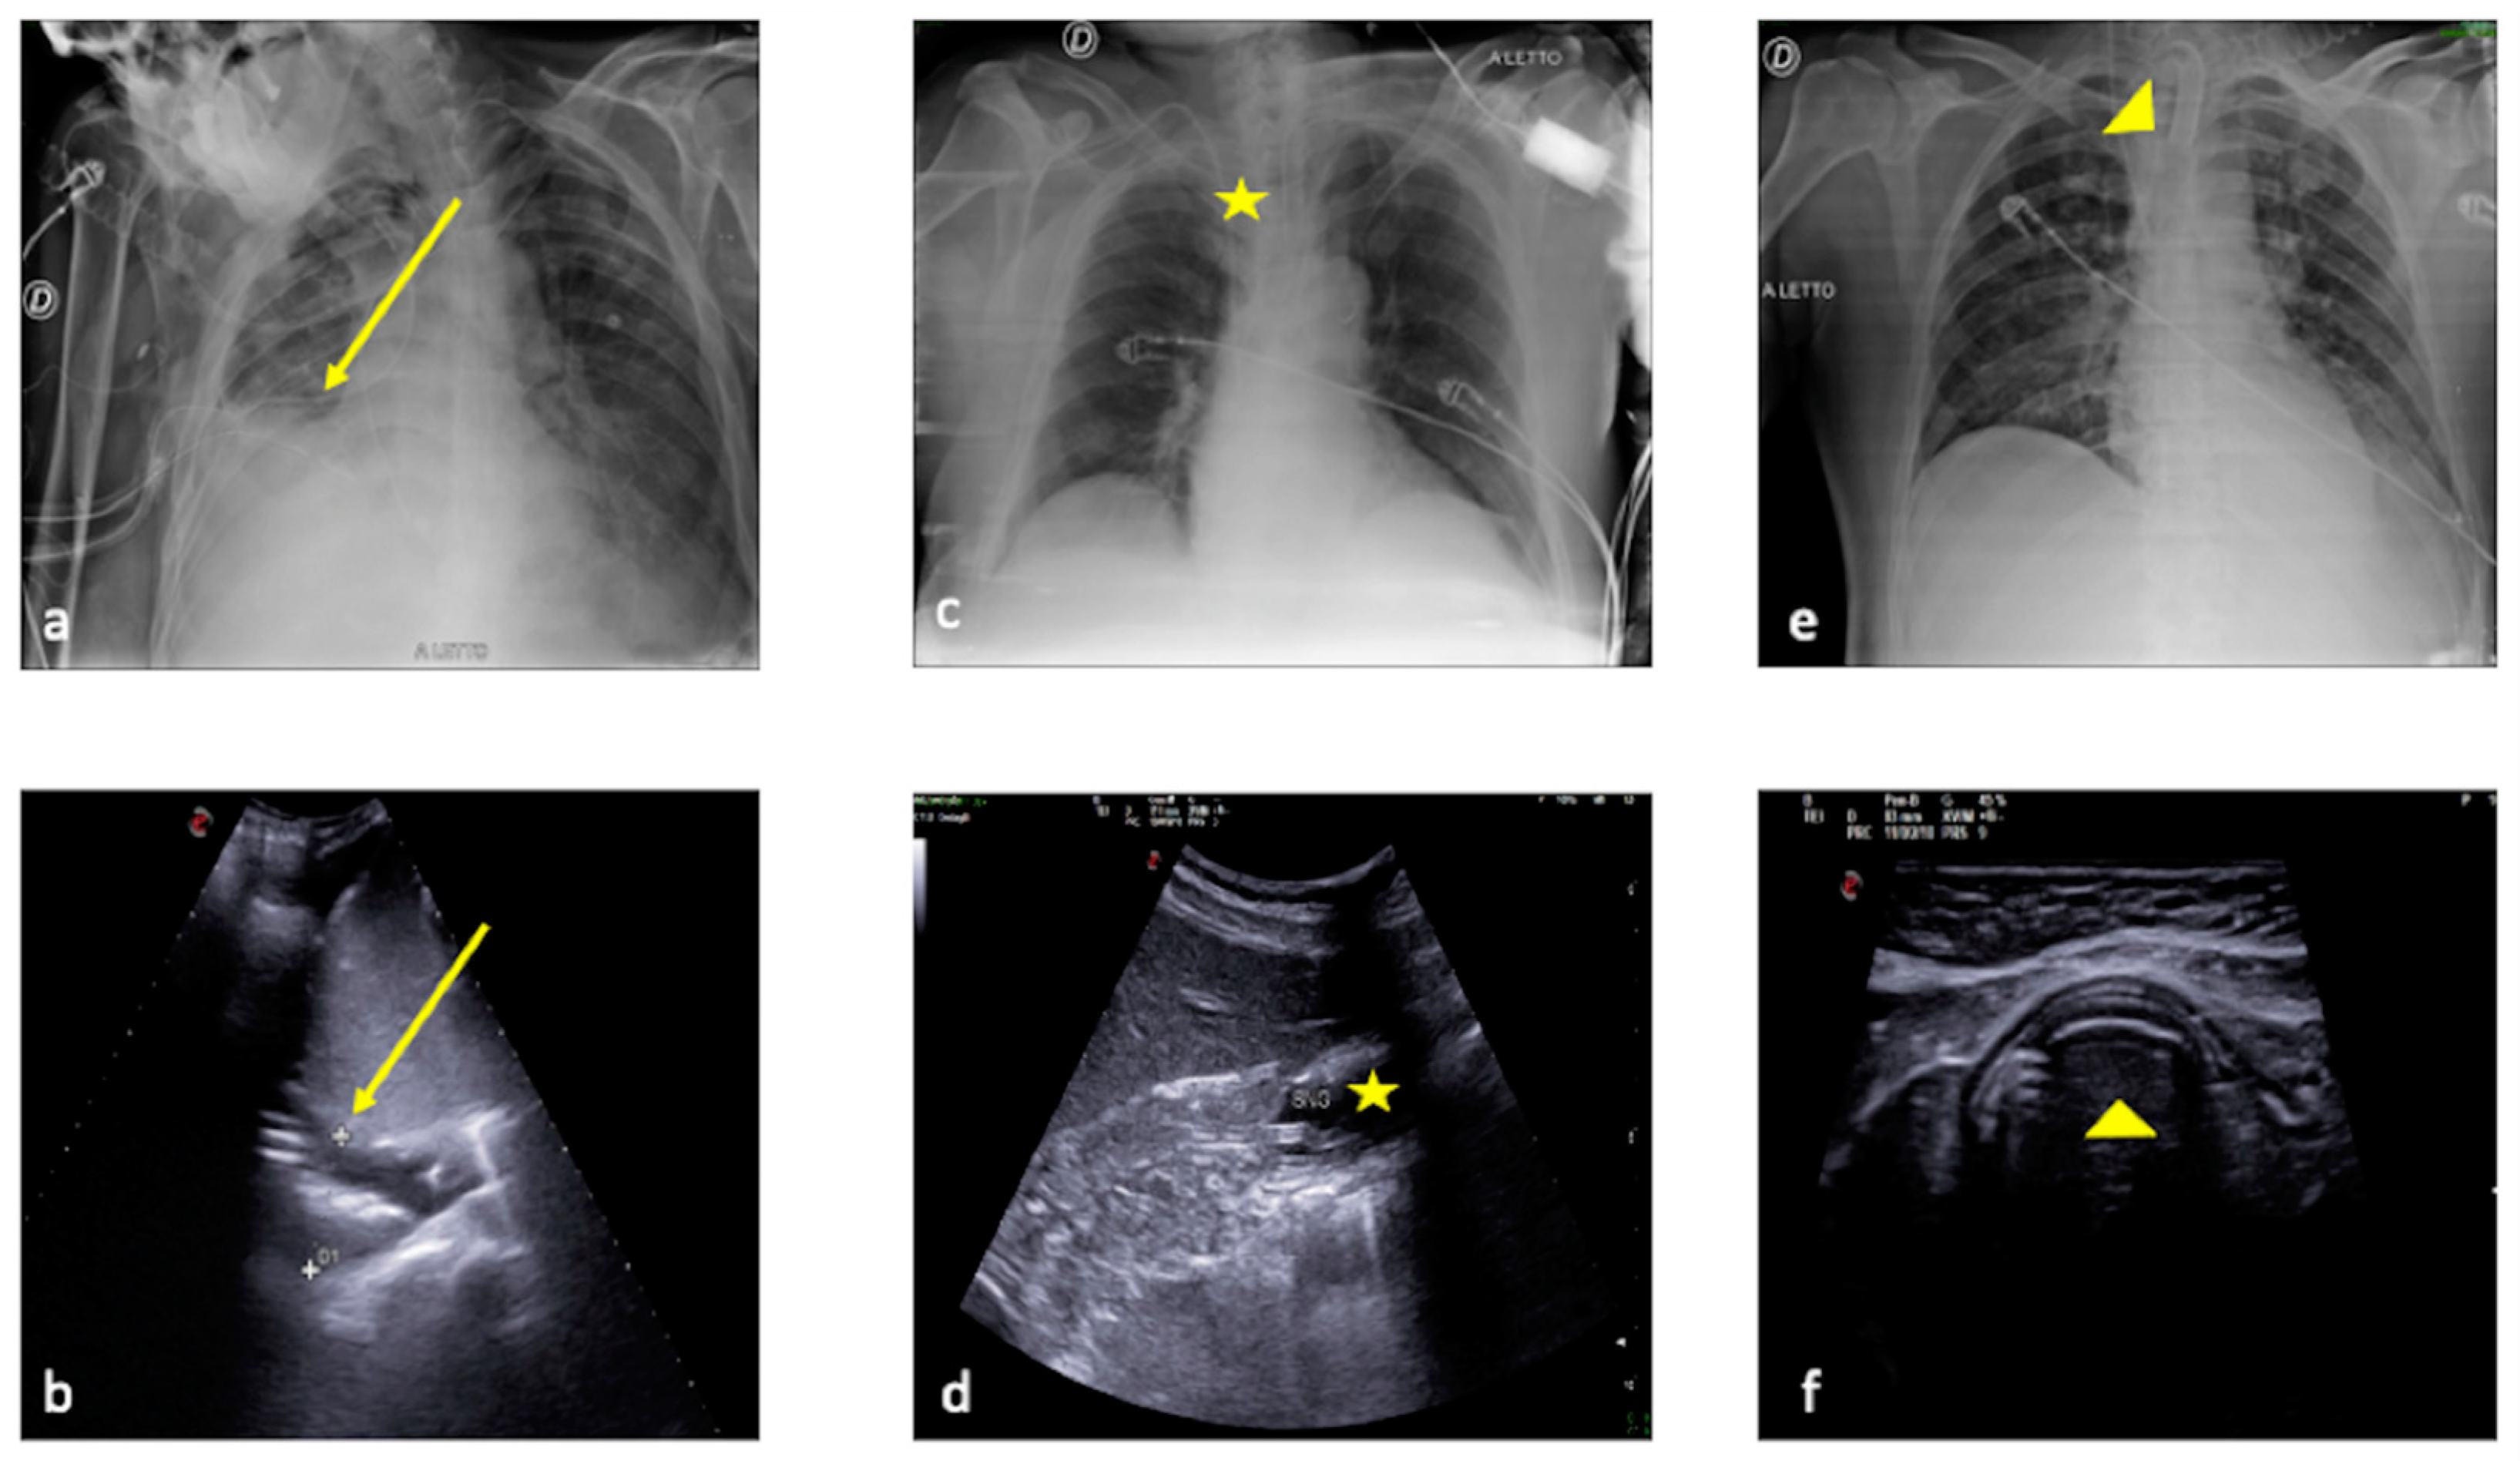

Figure 12 shows an example of CXR and LUS diagnostic integration in detecting and monitoring ARDS.

Figure 12.

A 57-year-old female patient with acute respiratory failure during interstitial pneumonia not related to SARS-CoV2 infection. Bedside CXR (a,c) and LUS (b). (a) The CXR revealed on the right side multiple small opacities with signs of interstitial thickening suggestive of an interstitial and alveolar infective process (a, arrow). (b) The LUS examination performed after 5 days showed in the middle right pulmonary field and on the left side a compact appearance of B-lines (b, arrowheads) associated with some areas of parenchymal consolidation (b, star) with an irregular pleural line (b, arrow) that was suggestive of ARDS complication, according to the clinical worsening refractory to therapies. (c) The CXR confirmed massive involvement of the interstitial compartment and bilateral consolidation of the parenchyma with an internal air bronchogram suggestive of ARDS according to the clinical scenario (c, arrowheads).

Figure 13 shows an example of CXR and LUS diagnostic integration in detecting pulmonary contusion.

Figure 13.

A 33-year-old male patient referred to the ICU after major trauma by defenestration. Bedside CXR (a) and LUS (b,c). (a) The CXR revealed on the right side the presence of two thoracic tube drainages (a, arrows) after pneumothorax (not shown) with middle and lower right lung zones indicating several confluent opacities (a, arrowheads). (b,c) LUS revealed on the same side the presence of a thick pleural line (b,c, arrow) with multiple B-line artifacts (b, arrowheads) and hypoechoic alveolar consolidation (c, star) corresponding to lung contusion.